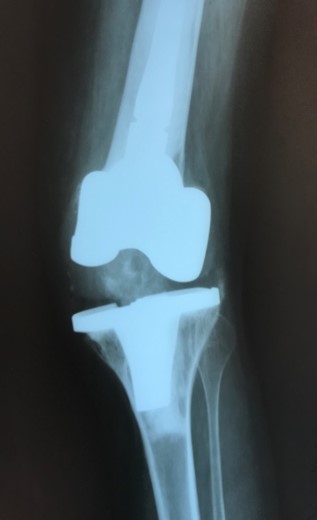

Проектування та виготовлення індивідуальних аугментів для заміщення  дефектів суглобів: М, 48р, асептична нестабільність онкологічного ендопротеза . Заміщення дефекту індивідуальним аугментом та ревізійним ендопротезом , фіксація БІС, ПММА